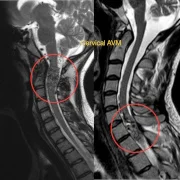

– Spinal Arteriovenous Malformation